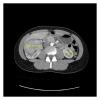

A 22-year-old female presented with back pain and was discovered to have a right-sided abdominal mass. Computed tomography (CT) scan revealed a 9 cm enhancing right upper pole renal mass with suspicion for tumor thrombus into the right renal vein and possibly the inferior vena cava (IVC). Magnetic resonance imaging (MRI) confirmed tumor thrombus into the inferior vena cava approximately 3 cm below the hepatic venous confluence. Open right radical nephrectomy with inferior vena cava thrombectomy was performed with removal of right kidney and tumor thrombus en bloc. Pathology revealed malignant epithelioid angiomyolipoma (EAML or PEComa). Epithelioid angiomyolipoma is a rare tumor of mesenchymal tissue that has the potential for local invasion and disease progression. Diagnosis of EAML was confirmed by pathology and immunohistochemistry. She was referred to medical oncology for discussion of surveillance versus potential adjuvant therapy and ultimately opted for close surveillance.